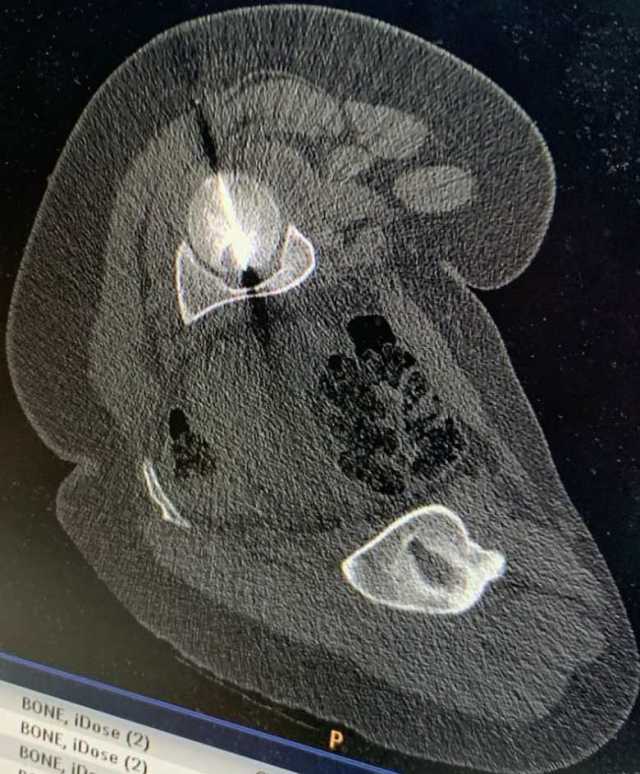

أجرى مستشفى الجامعة الأردنيّة، مؤخّرًا، تدخلًا علاجيًّا متقدّمًا في قسم الأشعة، استطاع من خلاله فريقٌ طبيٌّ متعدد الاختصاصات معالجة ورمٍ عظميّ في موقعٍ شديد الحساسيّة داخل رأس عظم الفخذ لمريضٍ ثلاثينيّ، ويُعد هذا الموقع من أكثر المواضع صعوبةً في الوصول إليها جراحيًّا، ما يجعل الخيارات التقليديّة محدودة ويزيد من تعقيد التعامل مع الحالة، لاسيما وأنّ المريض كان يُعاني من آلام حادّة أثّرت بشكل كبير على قدرته على الحركة وممارسة أنشطته اليوميّة.

وأُجري التدخل بإشراف استشاري الأشعة التداخليّة للجهاز العضلي والحركي الدكتور عمر البطوش، واستشاري جراحة العظام والمفاصل وجراحة ترميم مفاصل الورك والركبة وأورام العظام الدكتور باسم حداد، واستشاري أول التخدير والإنعاش والعناية الحثيثة الأستاذ الدكتور خالد الزبن، وبمساندة فريقٍ فنيٍّ وتمريضيٍّ متخصّص.

وبيّن البطوش، أنّ الفريق الطبي نجح في الوصول إلى مركز الورم بدقة عالية باستخدام تقنيّة التصوير الطبقيّ المحوريّ (CT Scan)، تلا ذلك إجراء الكي بالتقنيّة الحراريّة باستخدام المايكروويف (Microwave Ablation)، وهي من أحدث التقنيّات العالميّة في علاج أورام العظام دون الحاجة إلى التدخّل الجراحيّ المفتوح.

وأضاف البطوش، أنّ المريض أظهر تحسّنًا فوريًّا وملحوظًا منذ اليوم التالي للإجراء، ما يعكس دقة التقنيّة وفاعليّتها في استهداف الورم وتخفيف الألم بسرعة، وتمكين المريض من استعادة الحركة بصورة أفضل.

وفي هذا السياق، أكّد المدير العام للمستشفى، الأستاذ الدكتور نادر البصول، أنّ هذه التداخلات النوعيّة تعكس المستوى المتقدّم للكفاءات الطبية في المستشفى، والقدرة على توظيف أحدث التقنيات العلاجية لخدمة المرضى بأعلى درجات الأمان والفعالية، مُشيرًا إلى أنّ مستشفى الجامعة الأردنيّة يواصل ترسيخ مكانته كمركزٍ وطنيٍّ رائد في مجالات الأشعّة التداخليّة وعلاج أورام العظام، عبر الاستثمار المُستمر في التقنيّات الطبيّة الحديثة، وتعزيز بيئة التدريب والتعليم والبحث العلميّ، بما يُسهم في الارتقاء بجودة الرعاية الصحيّة على مستوى المملكة.